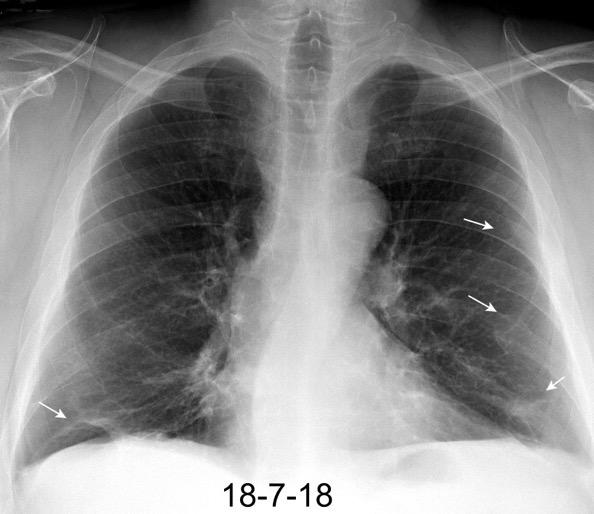

Linfoma de Hodgkin escleroso-nodular

Mediastinitis fibrosa. Fibrosis retroperitoneal.

10-20% de los casos de FM difusa

Reacción a Enf. Autoinmunes. (LED, AR)

Hematopoyesis extramedular

Metersigida / Radioterapia. Enf. inmunoglobulina IgG4. (Riedel, Colangitis, etc.)